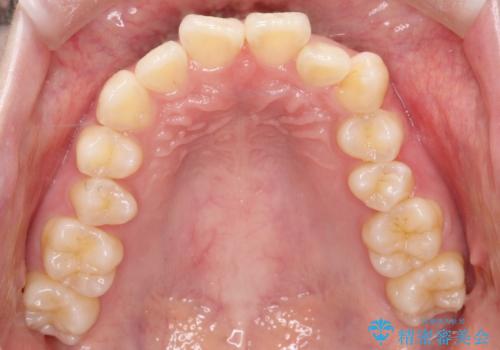

精密検査の結果、歯を並べるスペースの不足に加え、上下の歯列の正中(中心)が大きくズレていることが確認されました。突出した口元を下げ、顎の左右バランスを整えるためのスペースを確保するため、右上・左上・左下の4番目(第一小臼歯)を計3本抜歯する計画を立案。装置は、治療中の見た目にも配慮し、目立ちにくい審美ワイヤーを選択しました。

治療は、抜歯によって得られたスペースを活用し、前歯を後方へ移動させながら上下の中心を一致させる緻密な調整を行いました。

特に下顎の右方偏位に対しては、ワイヤーによる繊細なコントロールを行い、左右の咬合バランスを整えることに重点を置きました。2年半の治療期間を経て、突出していた前歯は理想的な位置に収まり、顎のズレも大幅に改善されました。